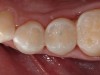

Figure 19  Immediate postoperative view of the completed restorations, after which the rubber dam was removed for verification of the occlusion.

Figure 19

Figure 20  Postoperative view of the completed posterior restorations.

Figure 20